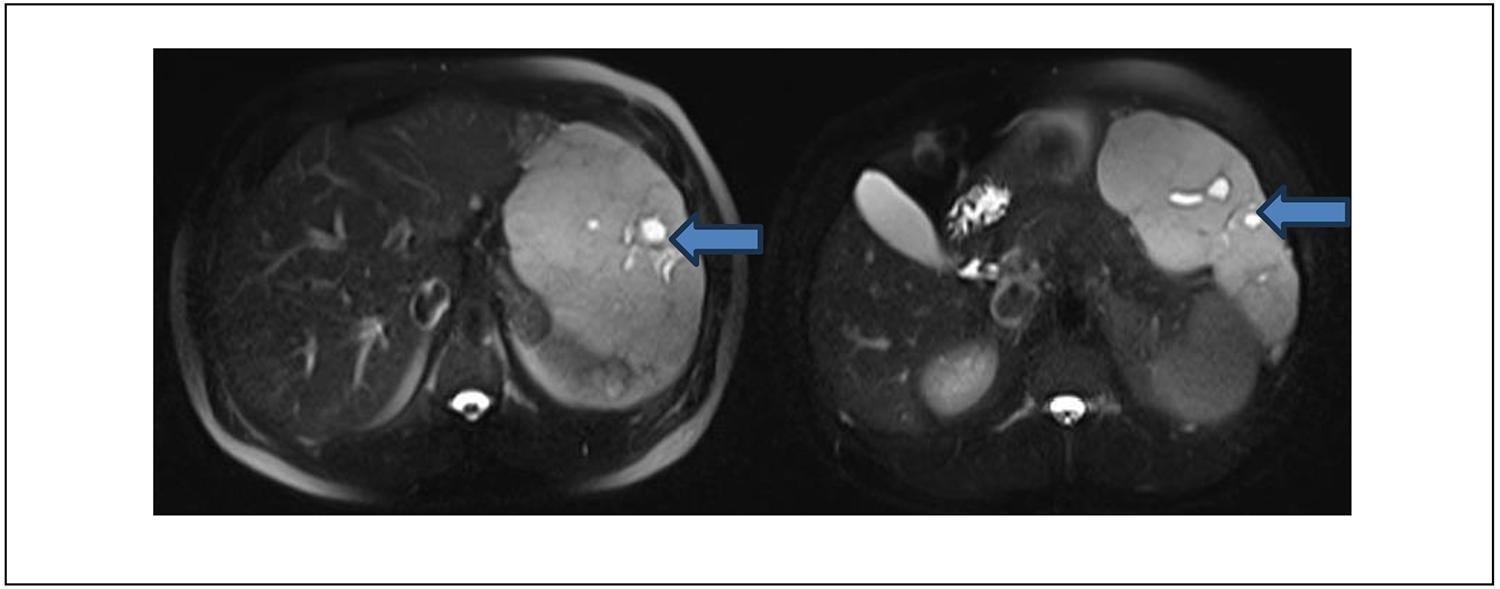

Los resultados de los análisis de sangre, incluyendo hemograma, enzimograma hepático, función renal y coagulación, fueron normales. La ecografía abdominal mostró un hígado heterogéneo con una lesión hiperecogénica en el lóbulo izquierdo. La tomografía computarizada de abdomen y pelvis con contraste endovenoso (TC) (Figura 1) reveló una imagen con características típicas de un hemangioma hepático: lesión voluminosa en el segmento II con captación de contraste discontinua y nodular periférica, con relleno centrípeto progresivo y longitudes de 179 mm x 97 mm x 174 mm. Por ello, se solicita Resonancia Magnética complementaria, (Figura 2) donde se visualiza dicha lesión hiperintensa en secuencia T2. Se identificaron dos imágenes hepáticas similares en los segmentos 6 (35 mm) y 7 (12 mm). No hubo dilatación de la vía biliar intra ni extrahepática.

Figura 1. Tomografía de abdomen y pelvis con contraste, donde se evidencia masa hepática en lóbulo izquierdo que desplaza y comprime estómago (flecha azul).La resonancia magnética abdominal confirmó la presencia de hemangiomas pequeños y un hemangioma gigante pediculado en el segmento II-III, presentando contacto con la pared abdominal, bazo y estómago, pero sin infiltración. (Figura 2).

Figura 2. Resonancia magnética que muestra cortes abdominales donde se observan la masa hepática, con realce en secuencia T2 (flechas azules).Los marcadores tumorales CEA, Ca 19-9 y alfafetoproteína fueron normales. Se decidió realizar una hepatectomía atípica laparoscópica con resección de parte de los segmentos II y III. Se retira la pieza por una incisión mediana, sin incidentes.